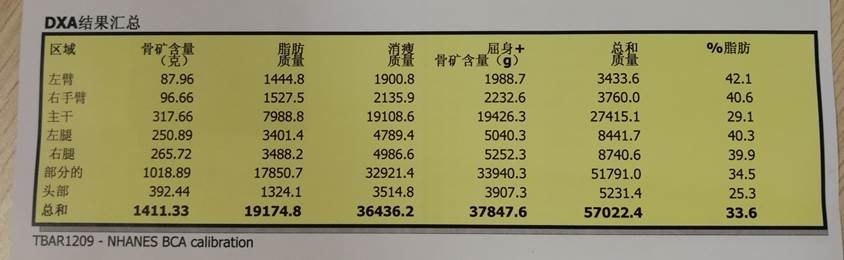

肌容量评估

DXA:计算肌容量

ASM/1.582=5.4kg/m2 <6

双手握力减弱(左侧 5.5kg 右侧 4.7kg 握力计)

行走速度<0.8m/s

诊断为腰椎管狭窄症;邻近节段退变;胸腰段后凸畸形;肌少症。并定制相关治疗措施,最后患者康复出院。

肌量检测方式:

肌量测量在诊断肌少症方面具有重要作用,主要测量方式存在不同方法,结果可根据身高或BMI 调整。

测定全身骨骼肌总量( skeletal muscle mass,SMM) 、四肢骨骼肌量( appendicular skeletal muscle mass,ASM) ,或特定肌群或身体某个部位的肌肉横截面积;

MRI和CT 被认为是无创性评估肌量的金标准,但还缺乏低肌量的测量界值;

双能X线吸收法(DXA) 使用更为广泛,目前被一些临床医生和研究人员用于肌量测量( 全身瘦肉组织量或四肢骨骼肌量测定) ,但不同品牌的设备所获得的结果并不一致;

肌量与身体大小有关,体型越大肌量通常越多,故量化肌量时,需要通过身高的平方、体重或体重指数调整SMM 或ASM 的绝对水平。

其中,DXA测量肌容量=四肢肌质量,即四肢肌质量(ASM)/身高2。